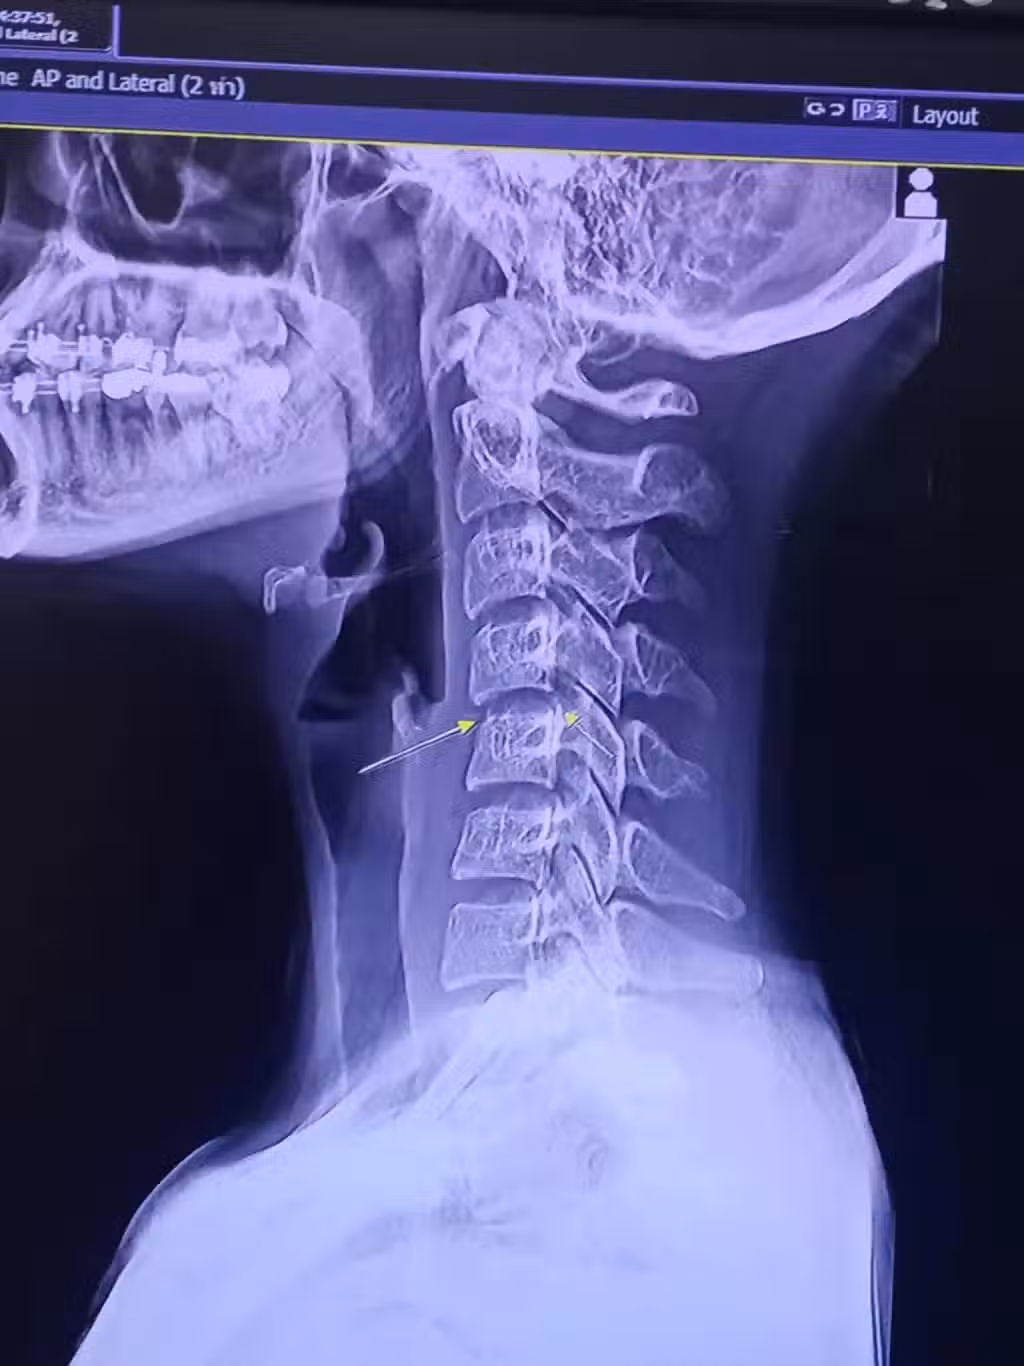

但事實其實是第一次按摩的時候就已經導致了她的頸部第三關節錯位,疼痛是因為頸部的錯位擠壓到了頸椎內部的神經元。